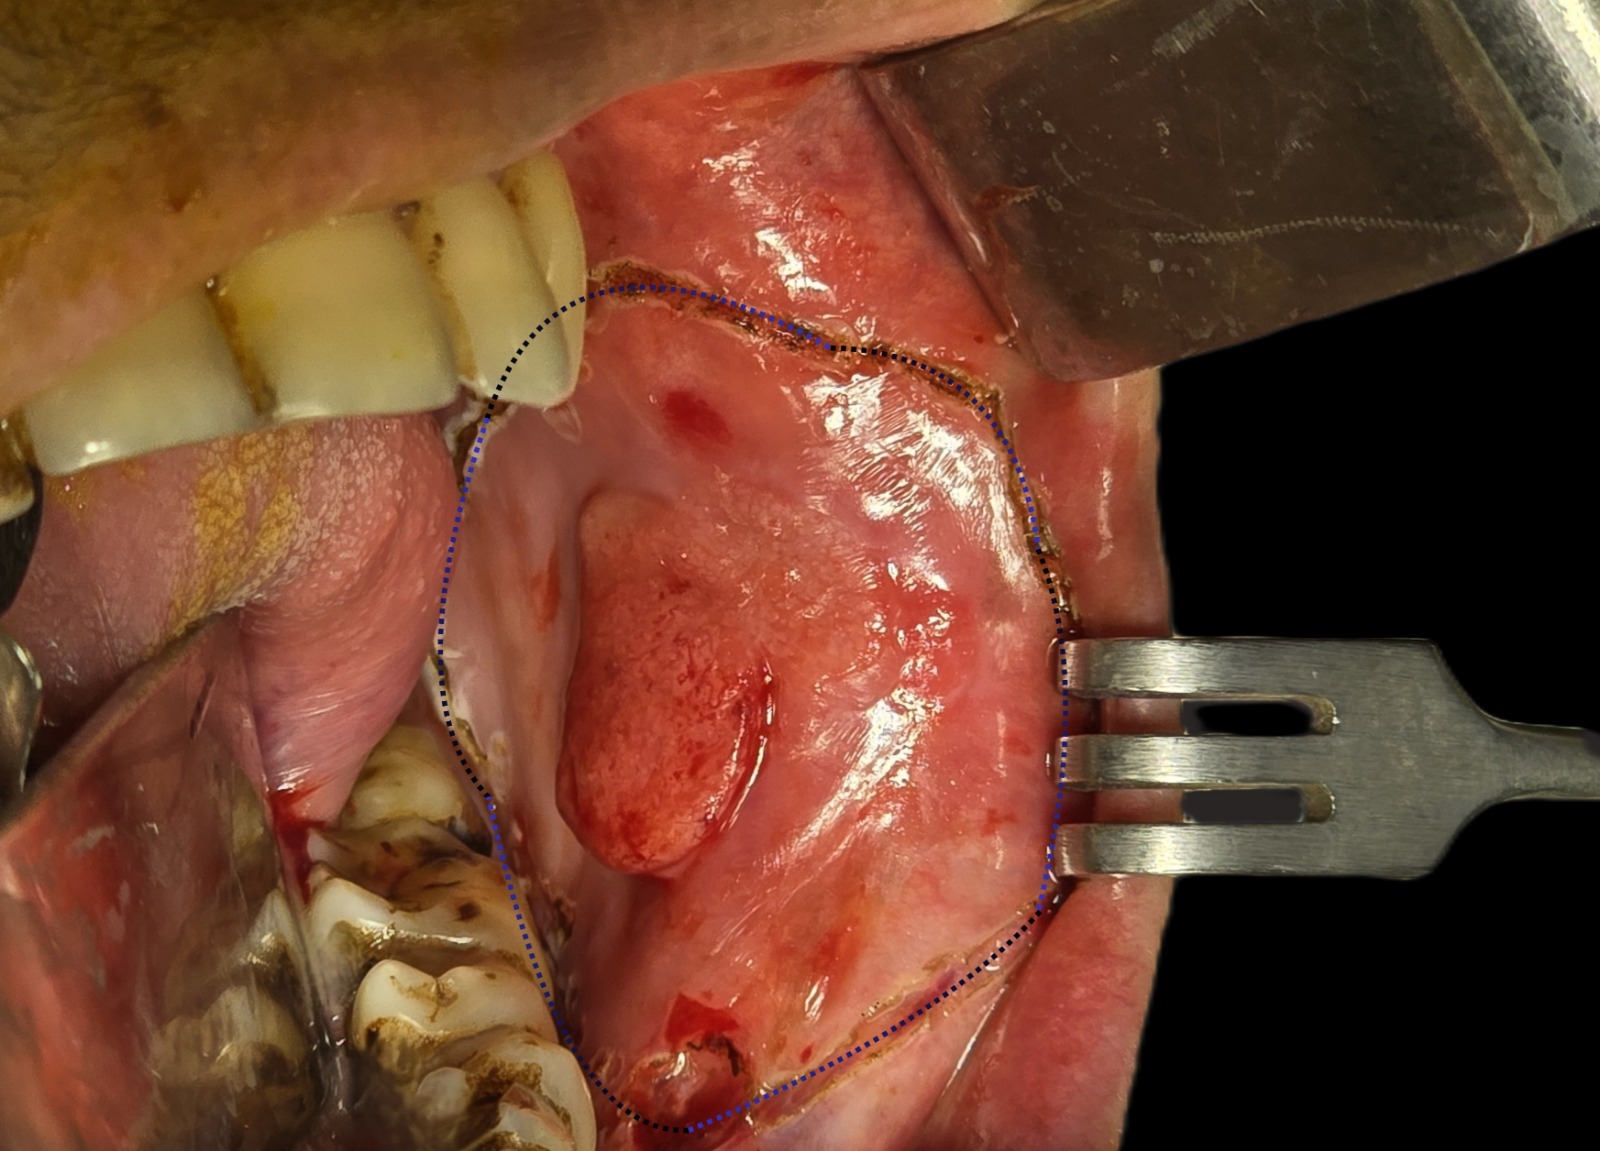

An experienced oral cancer specialist doctor in bangladesh studies symptoms, scans, and biopsy reports carefully. This step guides the safest treatment plan. Surgery often removes the cancer while protecting nearby nerves and muscles. Doctors may also combine surgery with radiation or other therapies if needed. The goal always focuses on removing disease and keeping normal mouth function.

An experienced oral cancer specialist doctor in bangladesh examines the mouth, reviews scans, and confirms the disease through biopsy. Treatment often involves surgery, followed by close monitoring and supportive therapy. Dr. Sajid Hasan works with a patient focused approach. He studies each case carefully before planning treatment. His experience in oral and maxillofacial surgery helps protect healthy tissue while removing cancer growth.

An experienced oral cancer specialist doctor in bangladesh studies each case before planning surgery. Doctors review scans, examine the mouth, and confirm the disease through biopsy results. Dr. Sajid Hasan has treated many oral disease cases through oral and maxillofacial surgery practice. His clinical experience helps guide treatment decisions that protect speech, chewing ability, and facial structure after tumor removal.